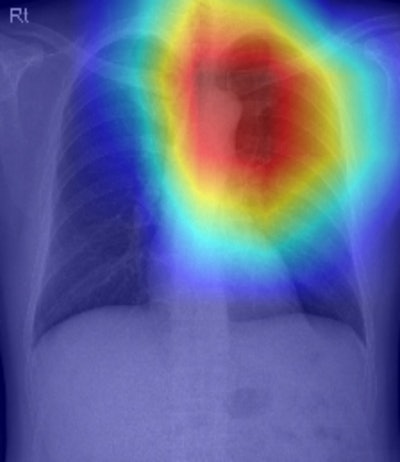

A representative case showing the prognostic value of CXR-Age from a chest x-ray of an individual who received a health check-up. The male individual’s chronological age was 56 years old. CXR-Age estimated biologic age of 68 years old. The Grad-CAM indicates a prominent aortic knob and upper thoracic spines. The patient died after seven years of lung cancer. Image courtesy of Radiology: Artificial Intelligence.

In addition, the group noted that gradient-weighted class-activation maps (Grad-CAM) generated by the algorithm mainly indicated the heart, aortic knob, upper lung parenchyma, mediastinum, and lower cervical and upper thoracic spines as areas that contributed to its age estimate. Changes in these areas, such as dilatation, calcification, and tortuosity, could represent the aging process, they noted.